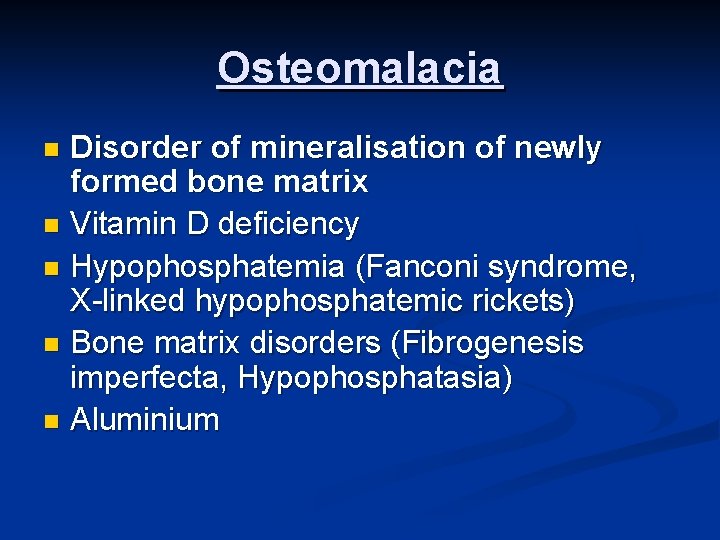

Osteomalacia Disorder of mineralisation of newly formed bone matrix n Vitamin D deficiency n Hypophosphatemia (Fanconi syndrome, X-linked hypophosphatemic rickets) n Bone matrix disorders (Fibrogenesis imperfecta, Hypophosphatasia) n Aluminium n